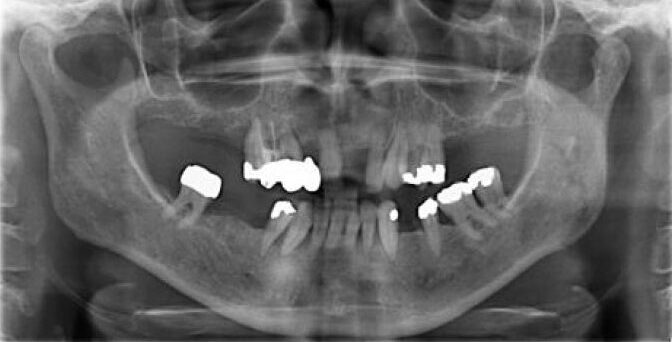

Vorher: Starke Vernachlässigung des Gebiss.

Patientin (geb. 1963) mit Parodontitis und zahlreichen defekten Zähnen im Ober- und Unterkiefer.